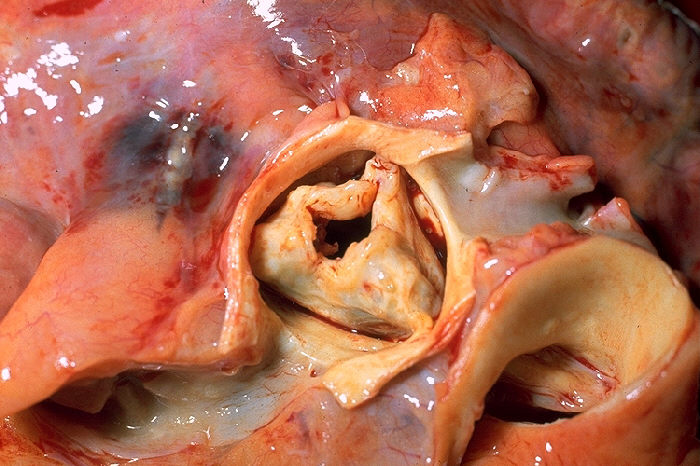

Chronic rheumatic heart disease develops when rheumatic fever-related valve scarring leads to stenosis with the classic fish-mouth appearance.

In chronic rheumatic heart disease, the chordae tendineae and cusps thicken as a result of the mitral valve being involved almost always.

Quite often the aortic valve is involved, which results in the commissures fusing together.

Other valves are less commonly involved and complications include infectious endocarditis.